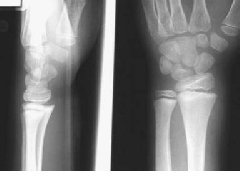

骨软骨瘤-恶变